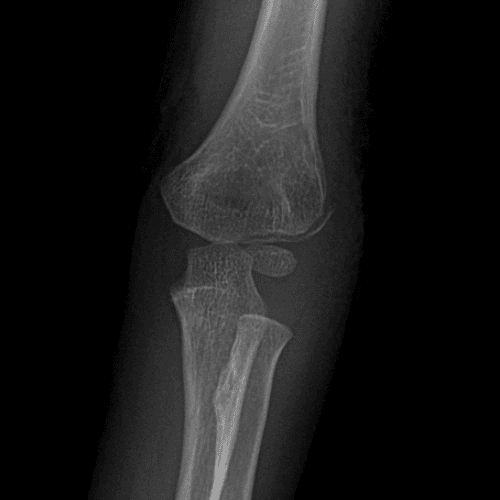

Simulates call by including subtle or difficult cases and some normals.

40 cases